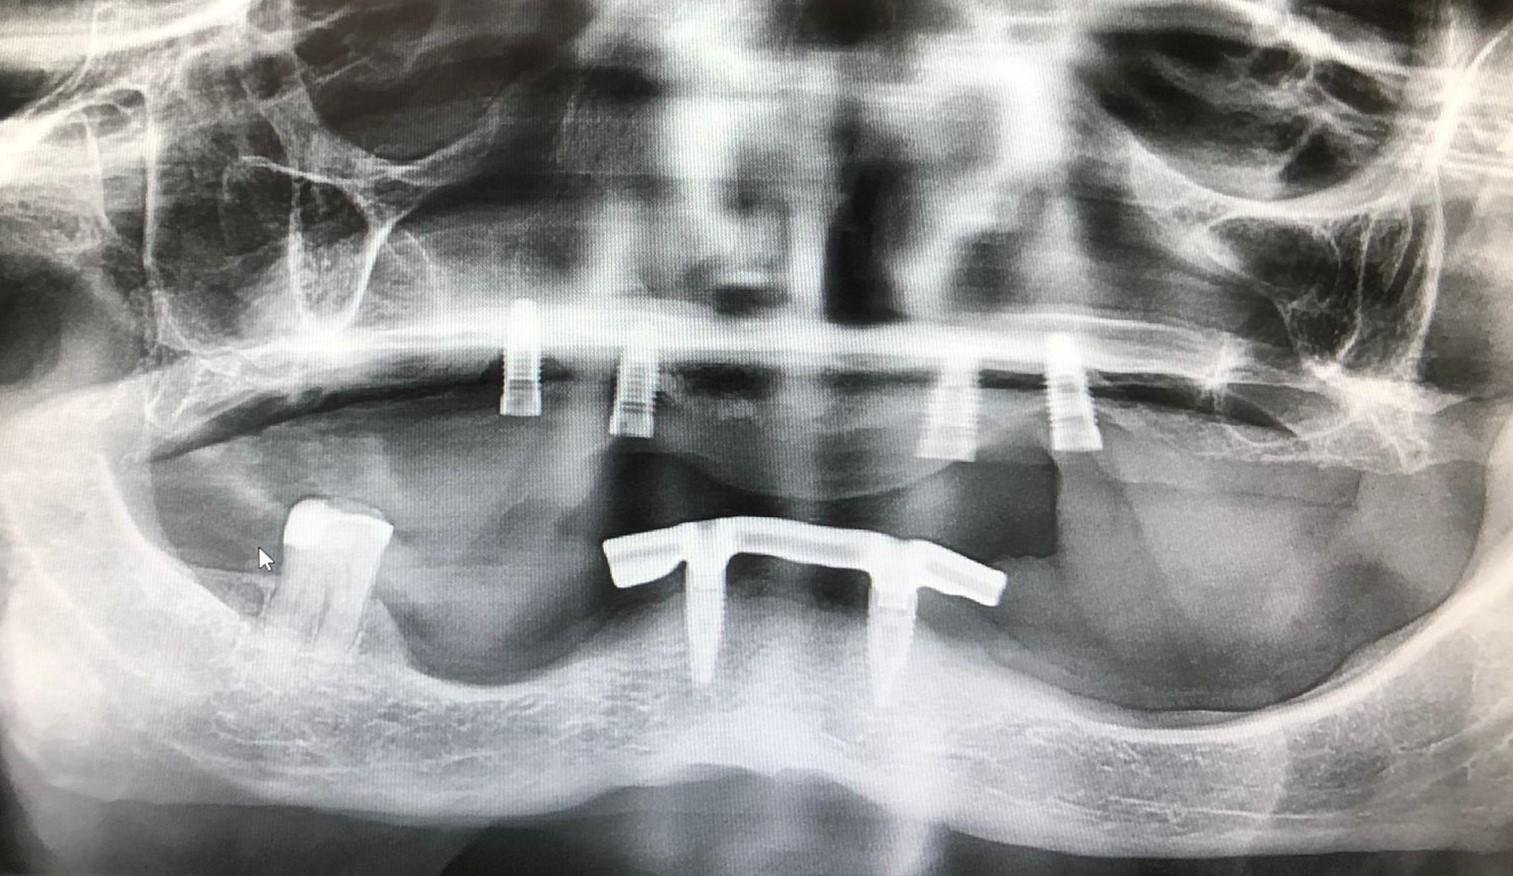

Buenas tardes, ¿me podrían decir qué implantes son los de la parte superior? Gracias. Saludos!

Aunque sería mejor confirmarlo con una rx periapical, yo diría que son Camlog (ahora BiohorizonsCamlog), y seguramente de diámetro 4,3. Destornillador hexagonal 1.27. Pero como te he comentado, mejor mándanos una periapical lo más paralela y nítida para poder confirmarte.

Y cuidado con esa pérdida que parece que tienen…

Me inclino más a implantes Nobel replace cónicos. La plataforma parece de 4.3 mm dorada.

La métrica de tornillo es 2 mm y el destornillador es unigrip.

Mucho ojo que tienen una periimplantitis de las buenas.

Pues también podría ser, lo que está claro es que es trilobular.